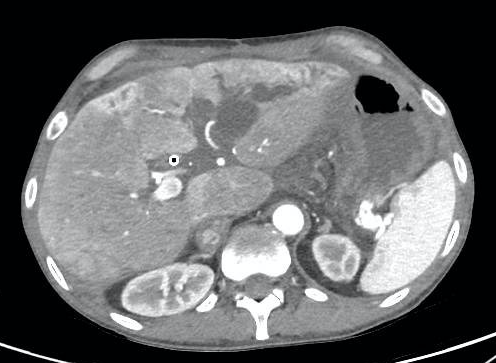

Case 2: a 52 y old man, with a MVT for diffuse portomesenteric thrombosis, Budd-Chiari syndrome and a thrombosed portocaval shunt. He showed cholestasis since 2 weeks of the procedure, initially related to drug toxicity, but progressively deteriorated, and biliary sludge was shown after several weeks, an ERCP failed, a PTC was done and a bile cast shown. Repeated ERCPs were done for cholangitis and stent exchange, and he developed intrahepatic massive biliary dilation (see figures 1 and 2). Over time, antibiotic resistant bacteria were isolated. A left liver lobe resection and bilioenteric anastomosis were done with the aim to stop these complications, but a severe sepsis developed and the patient subsequently died, 2 1/2 years after the MVT.